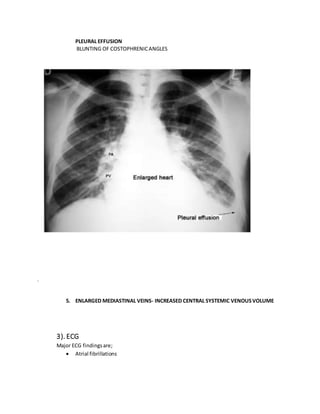

PLEURAL EFFUSION

BLUNTING OF COSTOPHRENICANGLES

5. ENLARGED MEDIASTINAL VEINS- INCREASED CENTRAL SYSTEMIC VENOUSVOLUME

3). ECG

Major ECG findingsare;

 Atrial fibrillations